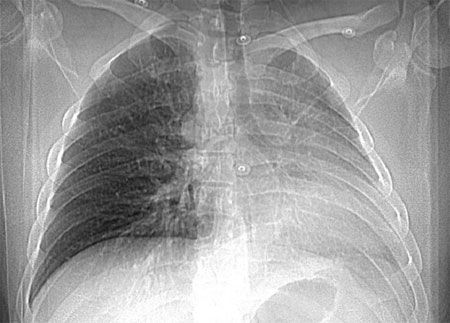

An ECG showed no significant abnormalities. A prominent right pulmonary artery, a right-sided aortic arch, cardiomegaly, and diminished left lung volumes were seen on a chest radiograph (Figure 1). An echocardiogram demonstrated normal chambers with no systolic dysfunction, no evidence of valvular or congenital heart disease, and normal pulmonary artery pressures. CT angiograms (CTAs) of the chest (Figures 2 and 3), a cardiac MRI scan (Figure 4), and a ventilation-perfusion (V/Q) lung scan (Figure 5) were also obtained. Pulmonary function tests (PFTs) revealed a moderate restrictive pattern (total lung capacity, 68% of predicted) with a mildly decreased carbon monoxide-diffusing capacity (76% of predicted) as per the ATS/ ERS task force (2005) standardization guidelines.

The chest radiograph may show ipsilateral cardiac and mediastinal displacement, ipsilateral smaller hemithorax, absent pulmonary artery shadow, ipsilateral hemidiaphragm elevation, ipsilateral absent or diminished pulmonary vascular markings, contralateral lung hyperinflation and herniation beyond the midline, or right-sided aortic arch.6